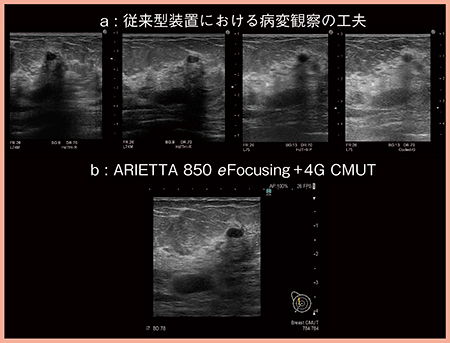

従来の装置では,良好な画像を得るために,さまざまな工夫を要することがあったが(図2 a),日立製の超音波診断装置ARIETTA 850では,新しい送受信技術eFocusingと半導体技術を用いた超広帯域プローブ4G CMUTにより,工夫をしなくても容易に,きわめて良好な画像が得られるようになった(図2 b)。

従来の送受信方式では,送信ビームの中央部で数本のビームを受信し,順にスキャンして画像を描出していたが,eFocusingでは,送信ビームの中央部でより多くのビームを受信し,すべての深度で受信ビームの加算を行った上で画像化する。さらに,バックグラウンドの処理速度も高速化したことで,浅部から深部までフォーカスの合った画像がリアルタイムに表示可能となった。また,従来のプローブは,生体とのインピーダンスの差を音響整合層で小さくして音波を生体に浸透しやすくしていたが,4G CMUTでは音響整合層が不要となり,生体に対して理想的なパルスを送信することができる。

図2 eFocusingと4G CMUTでは良好な画像を容易に取得可能